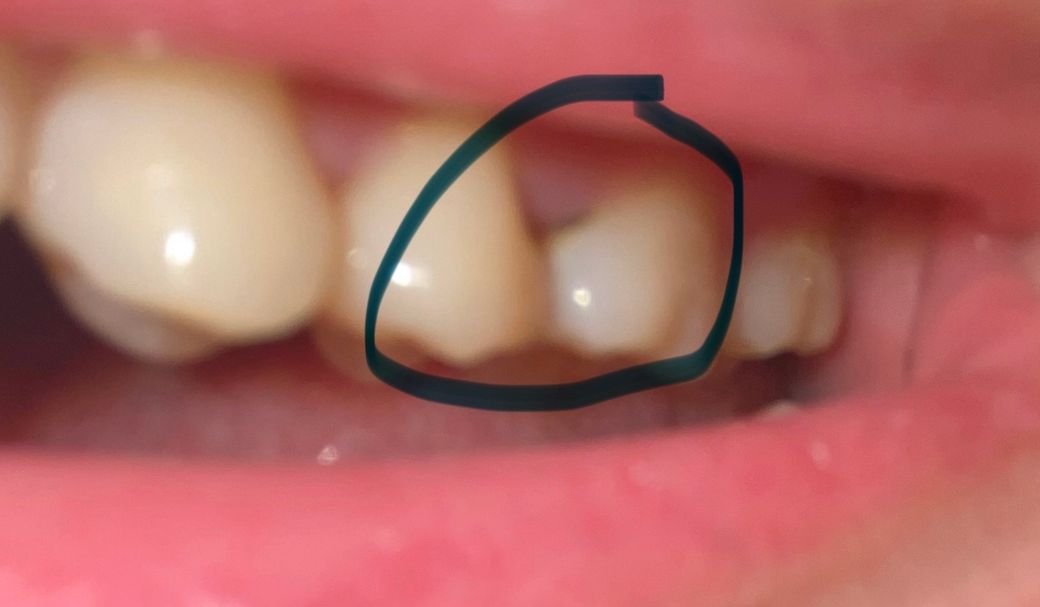

어금니 충치 질문입니다. 좀 봐주셨으면 좋겠습니다.

제가 치아에 충치가 생긴거 같아 치과를 가봤는데 충치가 맞고 육안으로 안 보이는 쪽에도 충치가 있어 인레이 치료를 해야할거 같다고 하셨는데 정말일까요? 일단 원래 가던 치과가 아니라 그냥 검진만 하러 간거라서 검진만 하고 나왔어요. 제가 좀 찾아보니까 레진으로도 가능하다고 하는데 인레이가 더 좋을까요? 레진은 좀 힘들까요? 그리고 인레이로 하면 치아 삭제를 얼마나 해야할까요? 교합면은 멀쩡한데 인레이 치료로 불필요한 삭제는 하는 것은 아닐까요? 질문으로 정리하면

• 1번 째 사진

사진에 보이는 부분은 레진으로도 치료가 가능할것으로 생각됩니다. 인접면에 충치가 있다면 인레이 치료를 하는것이 좋습니다. 인레이치료를 해야 한다면 인접면에도 충치가 있었을 가능성가능성이 있습니다.

육안상으로 보면 옆면에충치가 잇고 뿌리쪽에 충치가 잇는거 같습니다. 저 부위는 레진으로는 불가능하고 인레이나 크라운 치료를 하셔야될것같습니다.

1. 옆면 충치는 레진으로 해두면 음식물이 잘 끼고, 깨지므로 인레이를 일반적으로 추천합니다